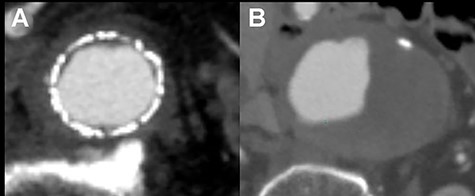

CT scan showing the increasing sac size of left CIAA with no endoleak (A) and aortic replacement with a Y-shaped vascular prosthesis performed with complete explantation of the endograft (B).

The infrarenal aorta up to the right common iliac artery and the left external iliac artery were exposed via a retroperitoneal approach. Proximal control was achieved by clamping midway between the renal arteries and the aortic bifurcation, and distal control was achieved by inserting an occlusion balloon into the right common iliac artery and clamping the left external iliac artery. The sac of the CIAA was opened, and many thrombi were noted around the stent graft. No backbleeding of the lumbar arteries or junctional bleeding of the stent was detected, and the entire endograft was removed easily. Abdominal aortic replacement with a Y-shaped vascular prosthesis (J Graft SHIELD NEO, bifurcated vascular prosthesis) was performed (Fig. 2B). Proximal and distal anastomoses were performed at the level of midway between the renal arteries and the aortic bifurcation where the endograft was fixed, and at the level of the right common and left external iliac arteries, respectively.